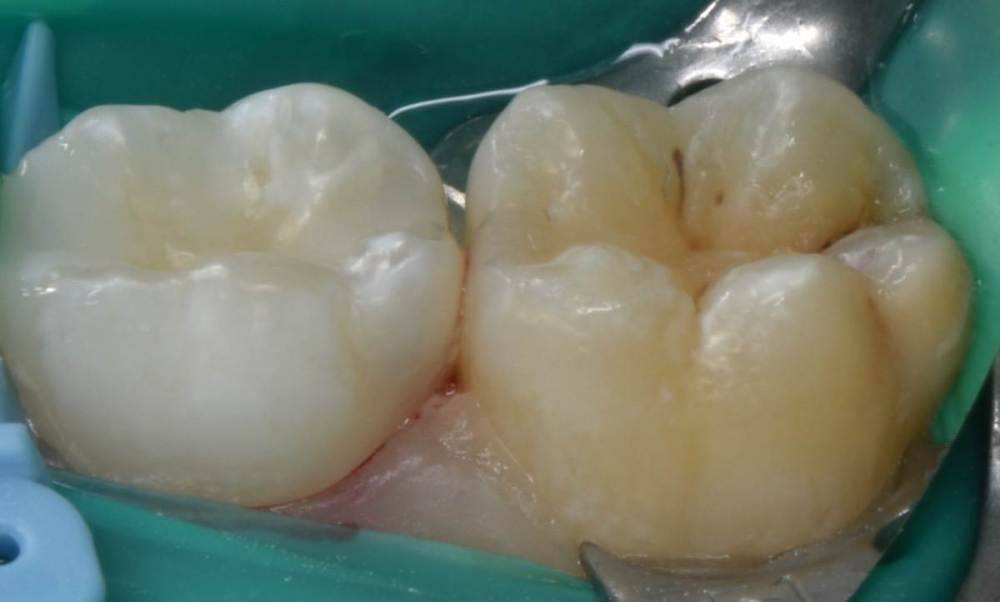

CRAZYDUCK Опубликовано 21 июля, 2022 Автор Поделиться Опубликовано 21 июля, 2022 Герметизация фиссур . Метод профилактики кариеса . В большинстве случаев для первых постоянных моляров . Прорезывание этих зубов часто проходит незаметно для родителей . Если проводить герметизацию , то с изоляцией и предварительной бережной очисткой от налёта . Как наладить гигиену у детей , как довести ее до идеала ? Я не знаююююююююю!!!!!! ??? Детям это не нужно , родители надеются на ответственность детей ( типа ты же уже большой / большая ). Но ! Обращаясь к родителям хочу сказать - примите этот факт , дети ещё не обладают достаточным уровнем ответсвенности . Участь детских стоматологов и гигиенистов - повторение мать учения , капля камень долбит не битьем , а частым падением . Режим спокойного попугая активирован . Рассказать , показать , записать на видео процесс качественной чистки зубов в стенах клиники и отправить это видео родителям для домашнего контроля . 4 1 Ссылка на комментарий